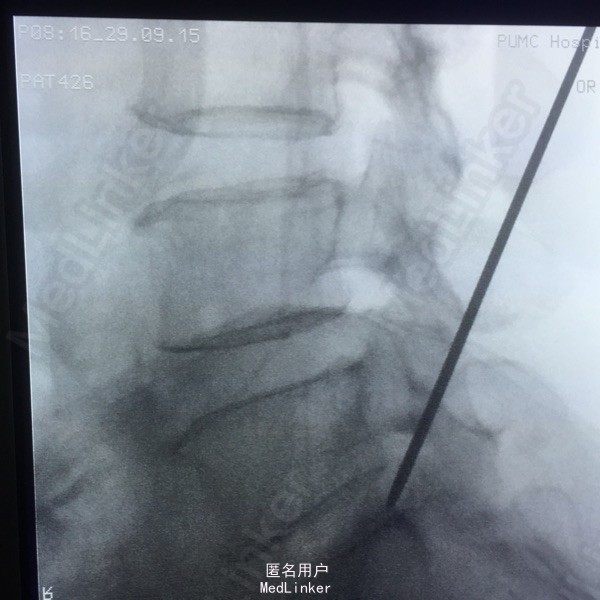

65岁女性,右下肢放射性疼痛2年半,保守治疗效果不佳 2年前曾行C5-6的ACDF术。

L5-S1左侧棘旁压痛(+),右小腿外侧针刺觉稍弱,右侧跟腱反射稍弱。 腰椎CT提示L5-S1间盘突出,偏右侧。 腰椎X线片提示髂嵴偏高,L5横突肥大。

L5-S1椎间盘突出 C5-6 ACDF术后 拟行椎间孔镜手术

因为穿刺通道比较狭小,进入椎间盘时偏杨氏,采用由内而外的方式减压神经根,用镜下弹性弯钳较好完成了神经根减压。